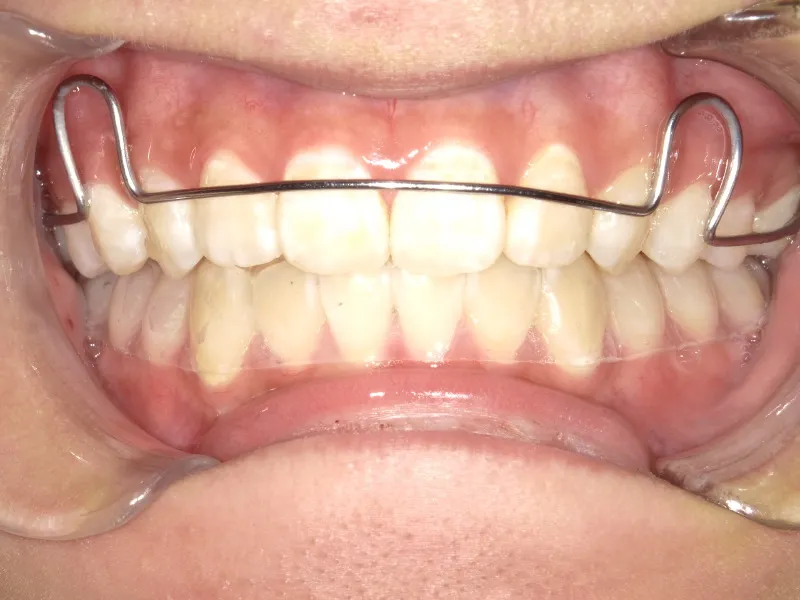

治療回数43回、7年4ヶ月の治療期間で矯正治療を終了しました。

主訴が改善され、ご満足頂きました。